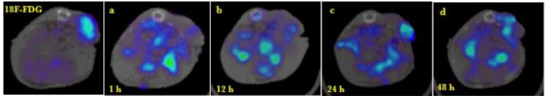

2.4. Biodistribution and Tumor Uptake in Mesothelioma Xenografts

| Time (h) | % Tumor | Tumor/Liver |

|---|---|---|

| 1 | 1.52 ± 0.15 | 6.61 ± 0.42 |

| 12 | 1.44 ± 0.23 | 6.21 ± 2.26 |

| 24 | 1.82 ± 0.18 | 8.46 ± 2.48 |

| 48 | 1.47 ± 0.31 | 5.71 ± 1.95 |